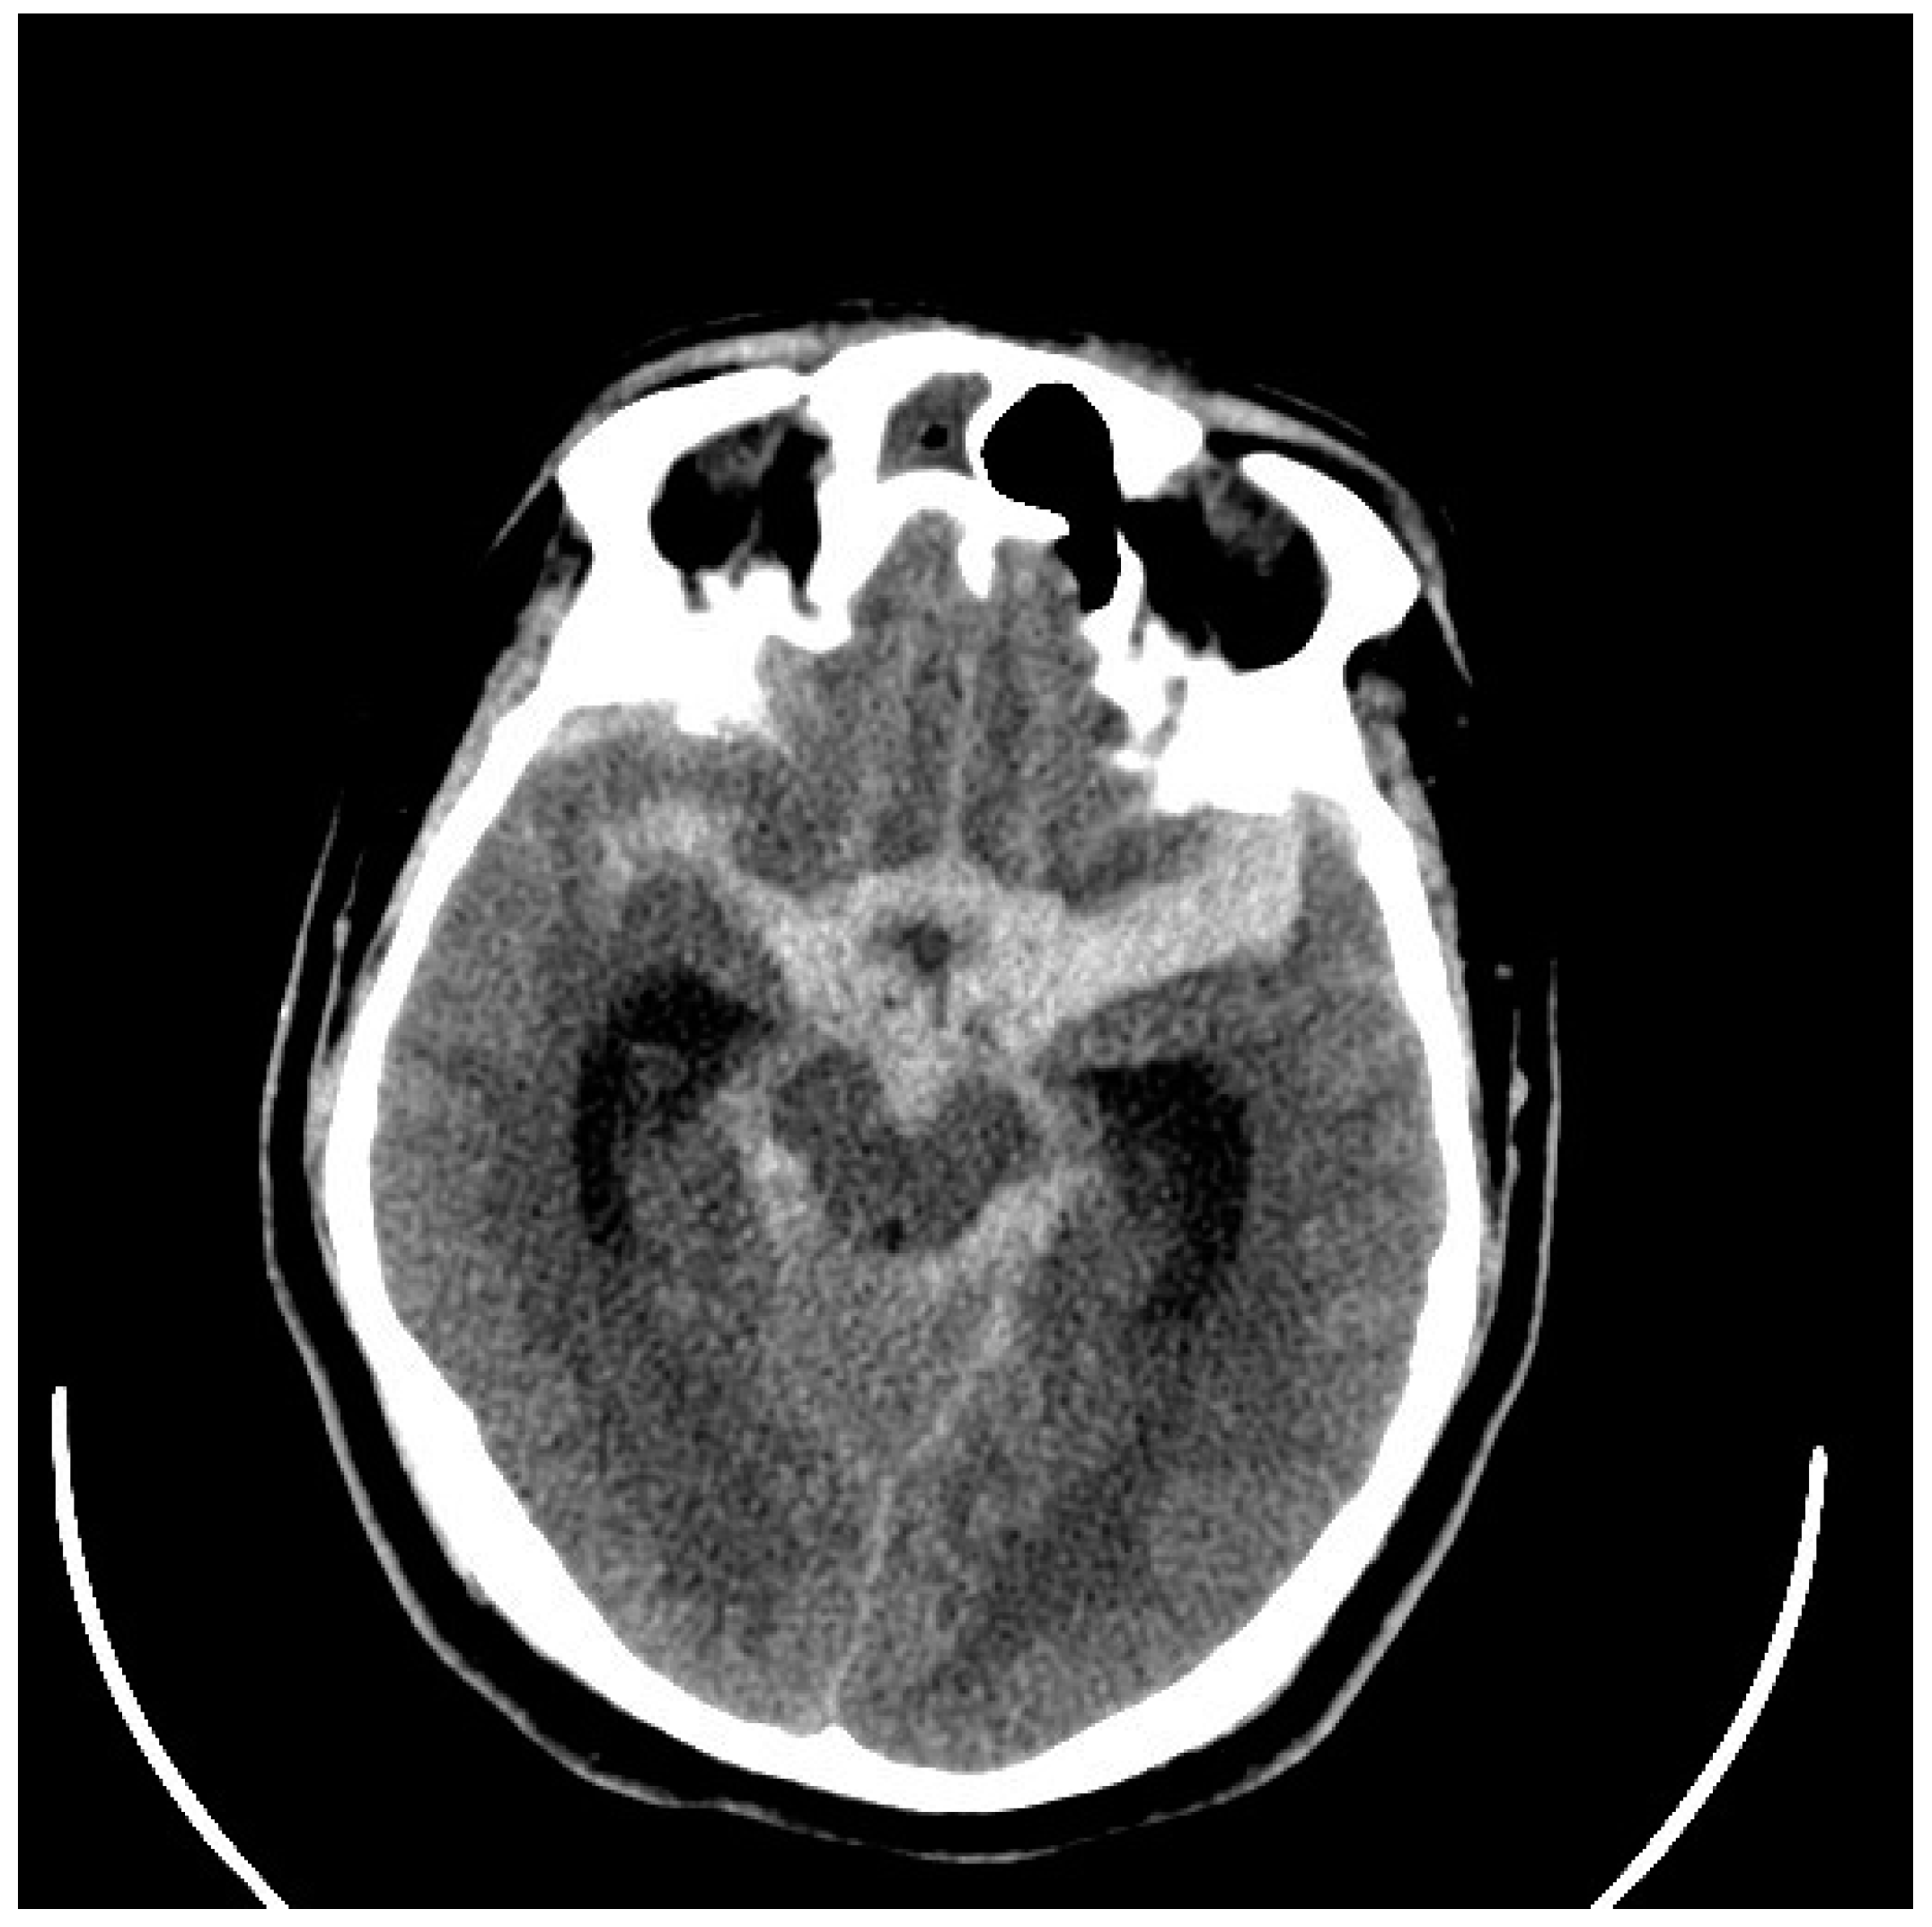

5. Diagnosis